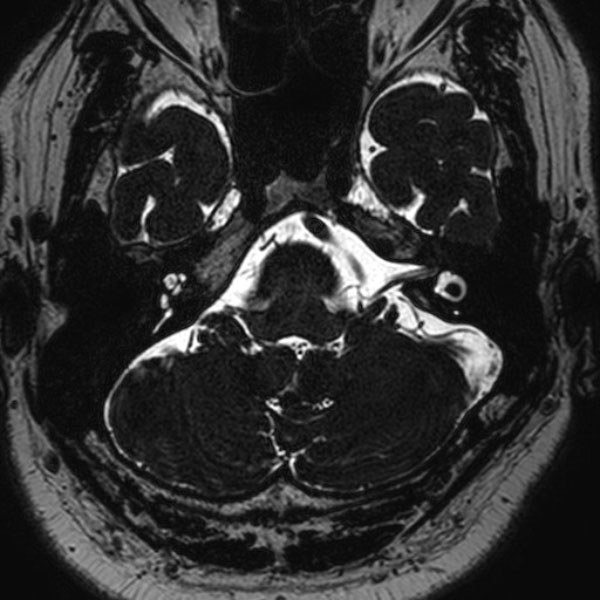

手術前

(MR1)